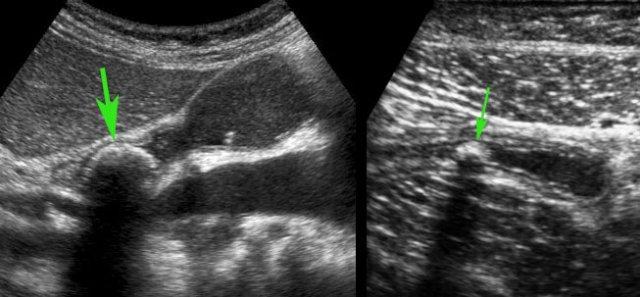

Hình ảnh Siêu âm này cho thấy ruột thừa viêm trên mặt cắt ngang (trái) và mặt cắt dọc (phải). Chương về Siêu âm trong viêm ruột thừa này được biên soạn dành cho tất cả những ai tham gia tích cực vào công tác Siêu âm bụng cấp cứu.

Siêu âm ruột thừa bình thường và ruột thừa viêm

Các đặc điểm siêu âm của ruột thừa bình thường được trình bày trong mục “Siêu âm đường tiêu hóa: giải phẫu bình thường”. Việc phân biệt ruột thừa viêm với ruột thừa bình thường thường khá dễ dàng trong hầu hết các trường hợp.

Ruột thừa bình thường – có thể quan sát thấy trong 20-30% trường hợp.

Ruột thừa viêm – có thể quan sát thấy trong 80-90% trường hợp.